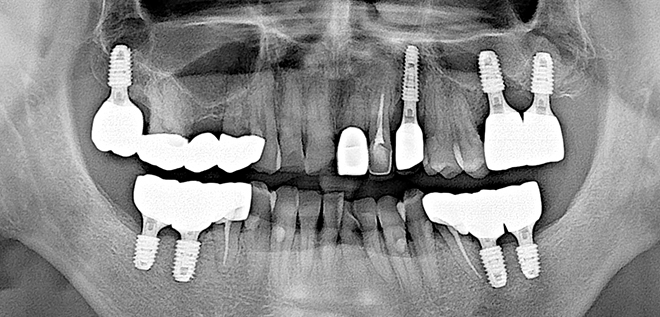

Before & After

어려운 임플란트 시술도

남양바른탑에서는 가능합니다.

• 01

3D CT시스템을 이용한 정밀진단

3차원 CT장비로 촬영 후 잇몸뼈의 상태 및 신경구조의 미세한 부분까지 진단합니다.